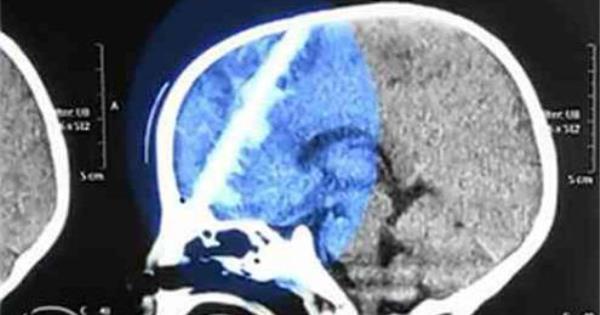

11月4號下午,一個名叫順順的孩子因為兩天高燒不退被送進了醫院。醫生在檢查之後發現,順順的鼻腔裡有類似筷子的物體,而後的CT更是讓醫生震驚了:這根柱狀物筆直地穿過了順順的大腦,直達另一側的顱骨,十分危險!  隨後在詢問家人情況時,醫生瞭解到,這筷子都已經是兩天前插入的了!當時順順吃飯時不小心摔了一跤,筷子就整根插進了鼻子,順順爺爺見狀,就給孩子直接拔了出來。雖然鮮血淋淋的,但是拔出後順順並沒有哪裡不舒服,所以家人就以為沒事了。誰知後來孩子就連續發燒,開始出現昏迷跡象,家人才趕緊將順順送到了醫院。原來爺爺拔筷子的時候並沒有將筷子全部拔出,而是折斷了,爺爺怕順順爸媽知道了責怪他,就一直瞞著,直到出事了才追悔莫及! 受傷兒童順順 目前,順順已順利完成手術,在順順頭顱裡的筷子已經被取出,並正在進行後續治療,但醫生稱可能會引起後遺症。  這則新聞真是讓人痛心,像這種筷子插入孩子頭部的新聞小編印象中真的是不止看到一次,小編在這裡真心想提醒家長們,孩子吃飯的時候,您也走點心吧!這些安全常識可一定要跟孩子灌輸: